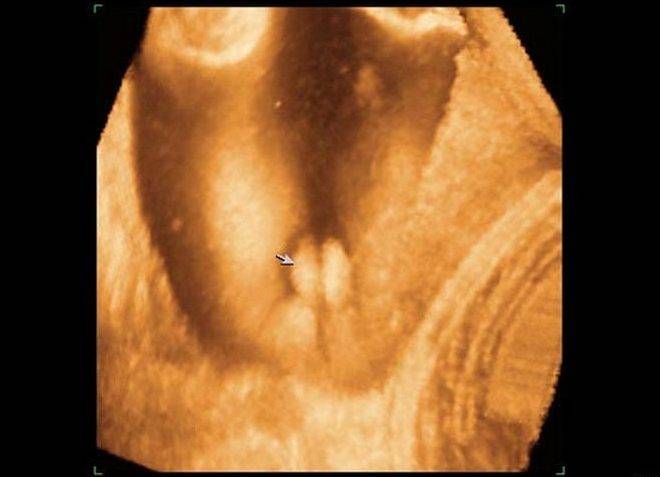

Врач не всегда может рассмотреть пол ребенка на плоской черно-белой картинке, получаемой в результате 2D УЗИ, поэтому, если будущим родителям не терпится узнать, кто у них будет, еще до момента рождения ребенка, назначается 3D ультразвук. Определить пол ребенка можно с 15 недели беременности.

Трехмерное УЗИ делают на ранних сроках беременности, чтобы лучше оценить состояние плода, удостовериться в том, что его пропорции соответствуют норме, все части тела находятся на своих местах. Визуализация здесь настолько качественная, что возможно разглядеть границы водной оболочки и тела самого эмбриона. При таком подробном изучении достаточно сложно ошибиться при замере различных параметров будущего младенца.

Сначала врач всегда измеряет длину плода, а затем — величину воротникового пространства, то есть шейной складки плода. Эта информация необходима для начальной проверки аномалий эмбриона

Также в процессе диагностики важно оценить, насколько развита носовая кость. Если она отсутствует или развита недостаточно, это признак хромосомной аномалии

Разглядеть ее на обычном УЗИ не всегда просто, поэтому нередко случаются ошибки. В 3D-режиме данные становятся точнее на 30%, то есть вероятность ошибки значительно снижается.